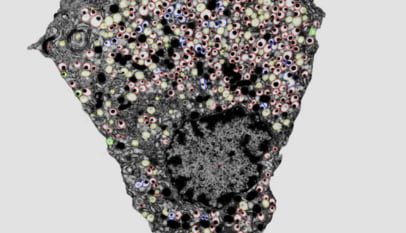

AS CÉLULAS QUE PRODUZEM INSULINA SÃO CHAMADAS DE CÉLULAS-BETA. Elas residem no pâncreas, mais especificamente em regiões do pâncreas conhecidas como Ilhotas de Langerhans. Estas células estão intimamente ligadas ao diabetes: no diabetes tipo 1, por exemplo, o sistema de defesa do corpo acaba atacando as próprias células-beta, prejudicando a produção de insulina, o que resulta no diabetes.

Além da insulina, as células-beta produzem também outros hormônios, importantes para a regulação do nosso corpo. Um outro detalhe interessante é que, além de fabricar, estas células também armazenam a insulina. Dessa forma, em casos de necessidade imediata de bastante insulina na corrente sangüínea, elas liberam seu estoque – o que é bem mais rápido e eficiente do que produzir do zero!